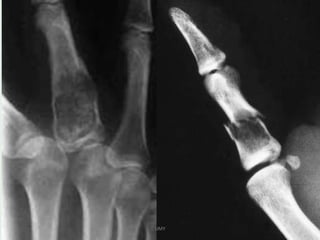

Enchondroma

UMY

• Common benign medullary cartilaginous neoplasm

• Usually found in children or young adults which can

lead to pathological fractures or undergo malignant

degeneration.

• 3-10 % of all bone tumours and 12-24 % of benign

bone tumours

• Enchondromas are most frequently diagnosed in

childhood to early adulthood with a peak incidence of

10-30 years.

• Complicated by a pathological fracture or malignant

transformation into a low grade chondrosarcoma

• (clinically if an enchondroma is painful in the absence

of a fracture, it should be considered malignant

IMAGING

• X-ray & CT

Typically enchondromas are small 1 - 2cm lytic lesions with

non-aggressive features.

narrow zone of transition

sharply defined scalloped margins : may have mild

endosteal scalloping

expansion of the overlying cortex may be present but there

should not be cortical breakthrough unless fractured

Chondroid calcifications may be present : rings and arcs

calcification-STIPPLED/PUNCTATE/POPCORN

no periosteal rxn.

• The majority of enchondromas more frequently arise in

the metaphyseal region,.

A cartilaginous lesion in an epiphysis is more likely to be a

chondrosarcoma .